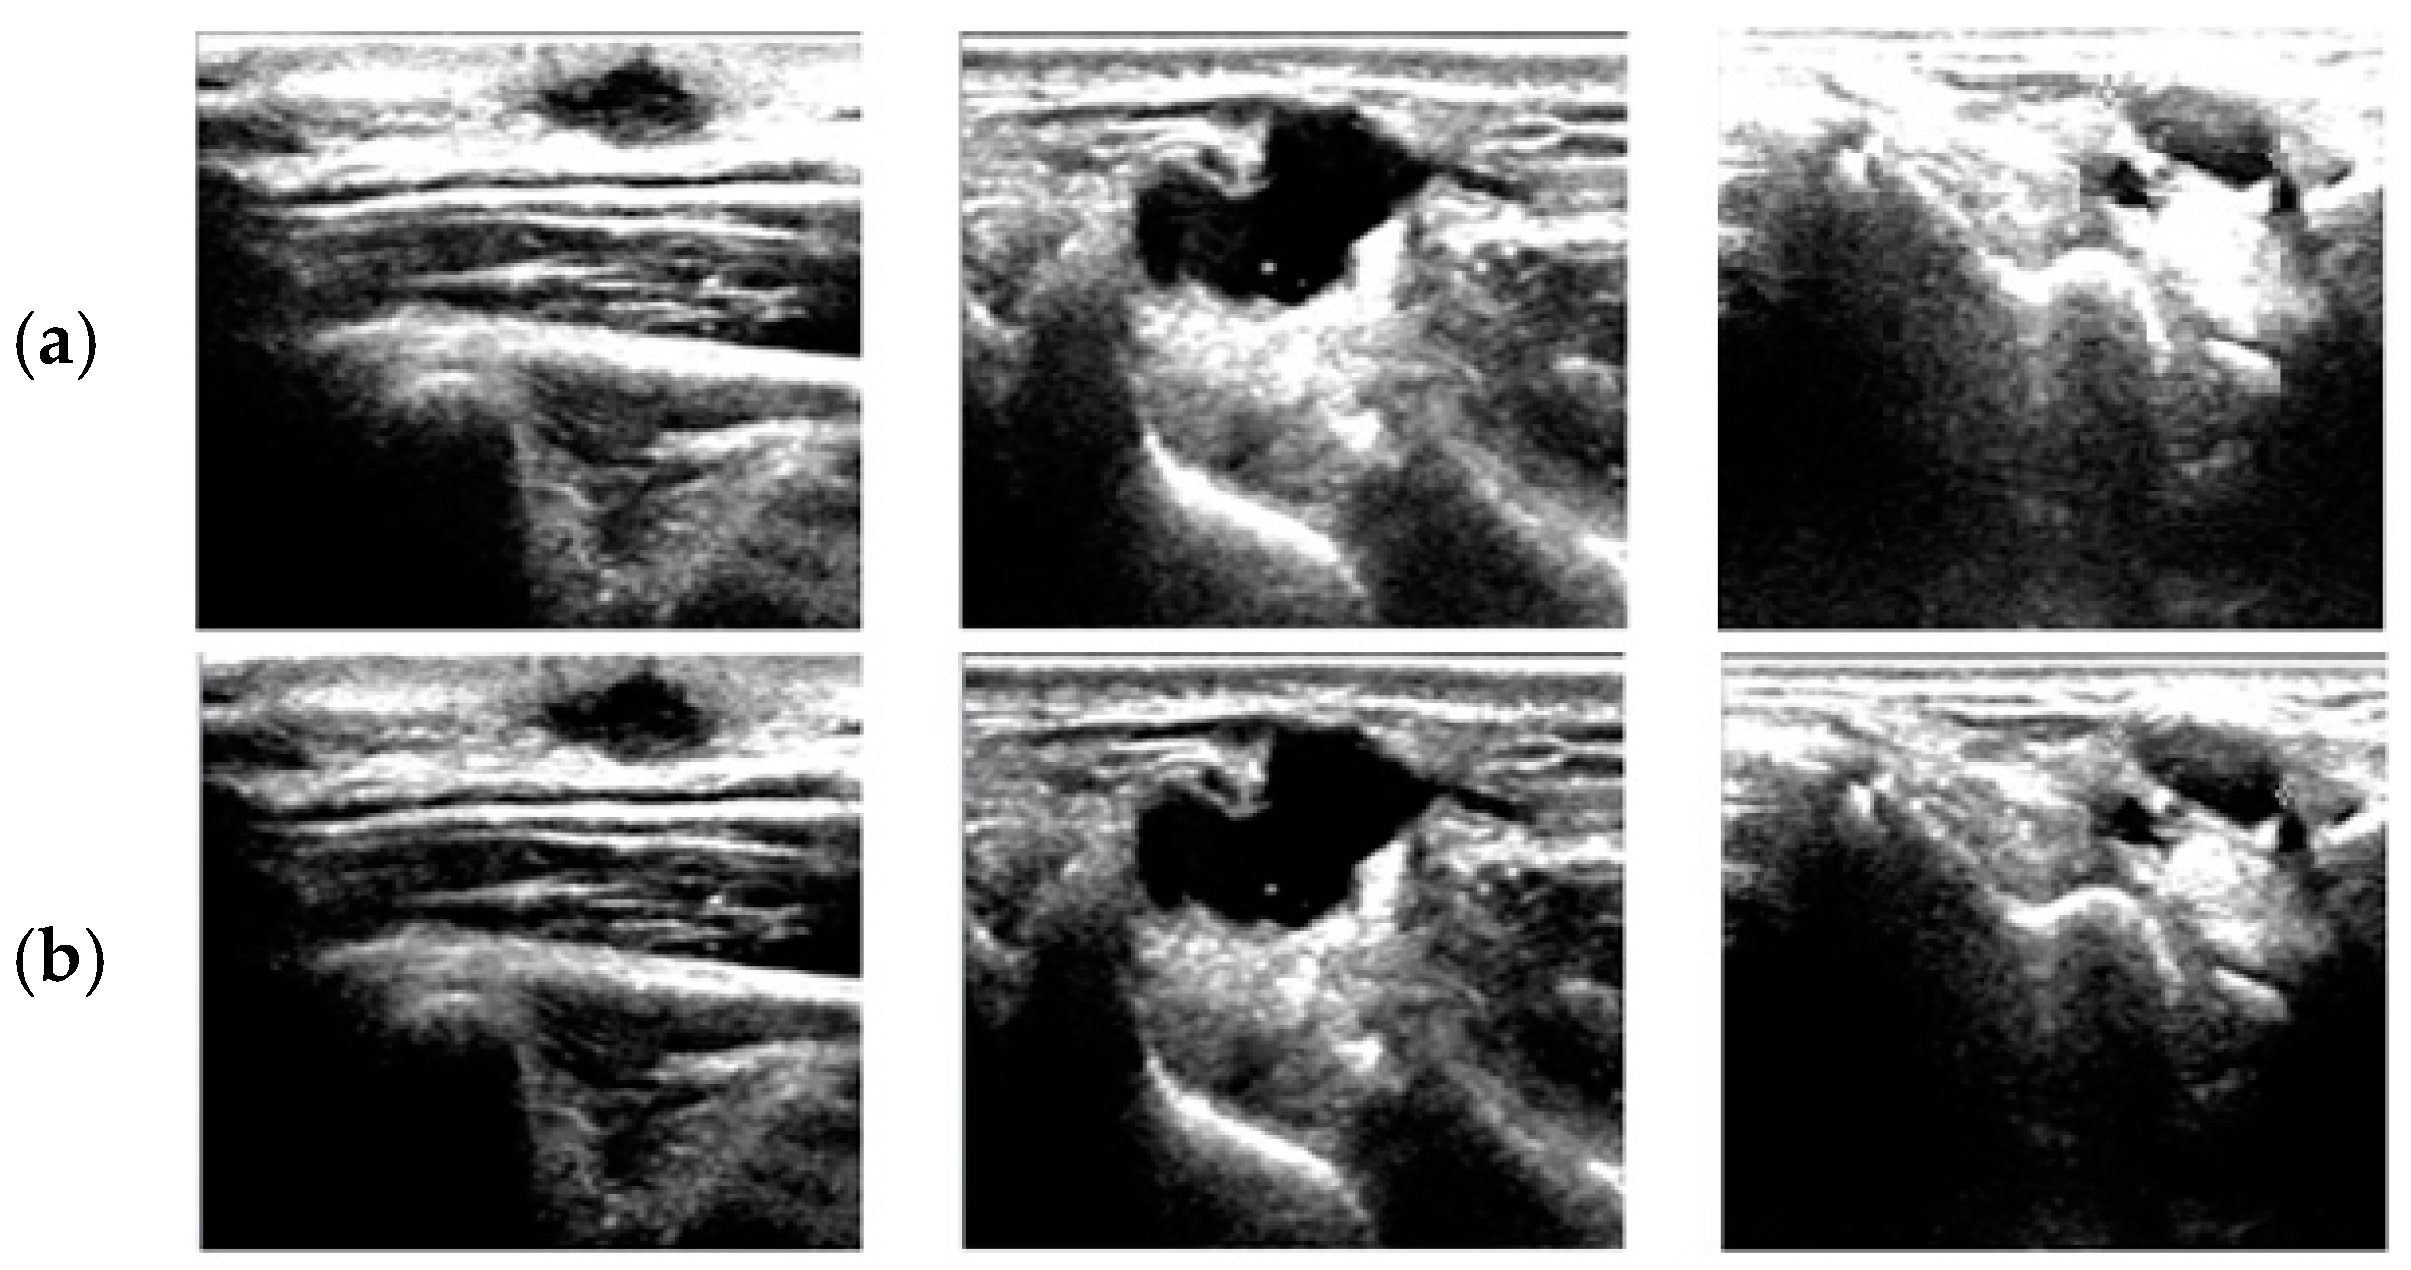

1. Introduction

2. Fuzzy Stretching with Trapezoid Membership Function in Image Enhancement

4. Results and Discussion